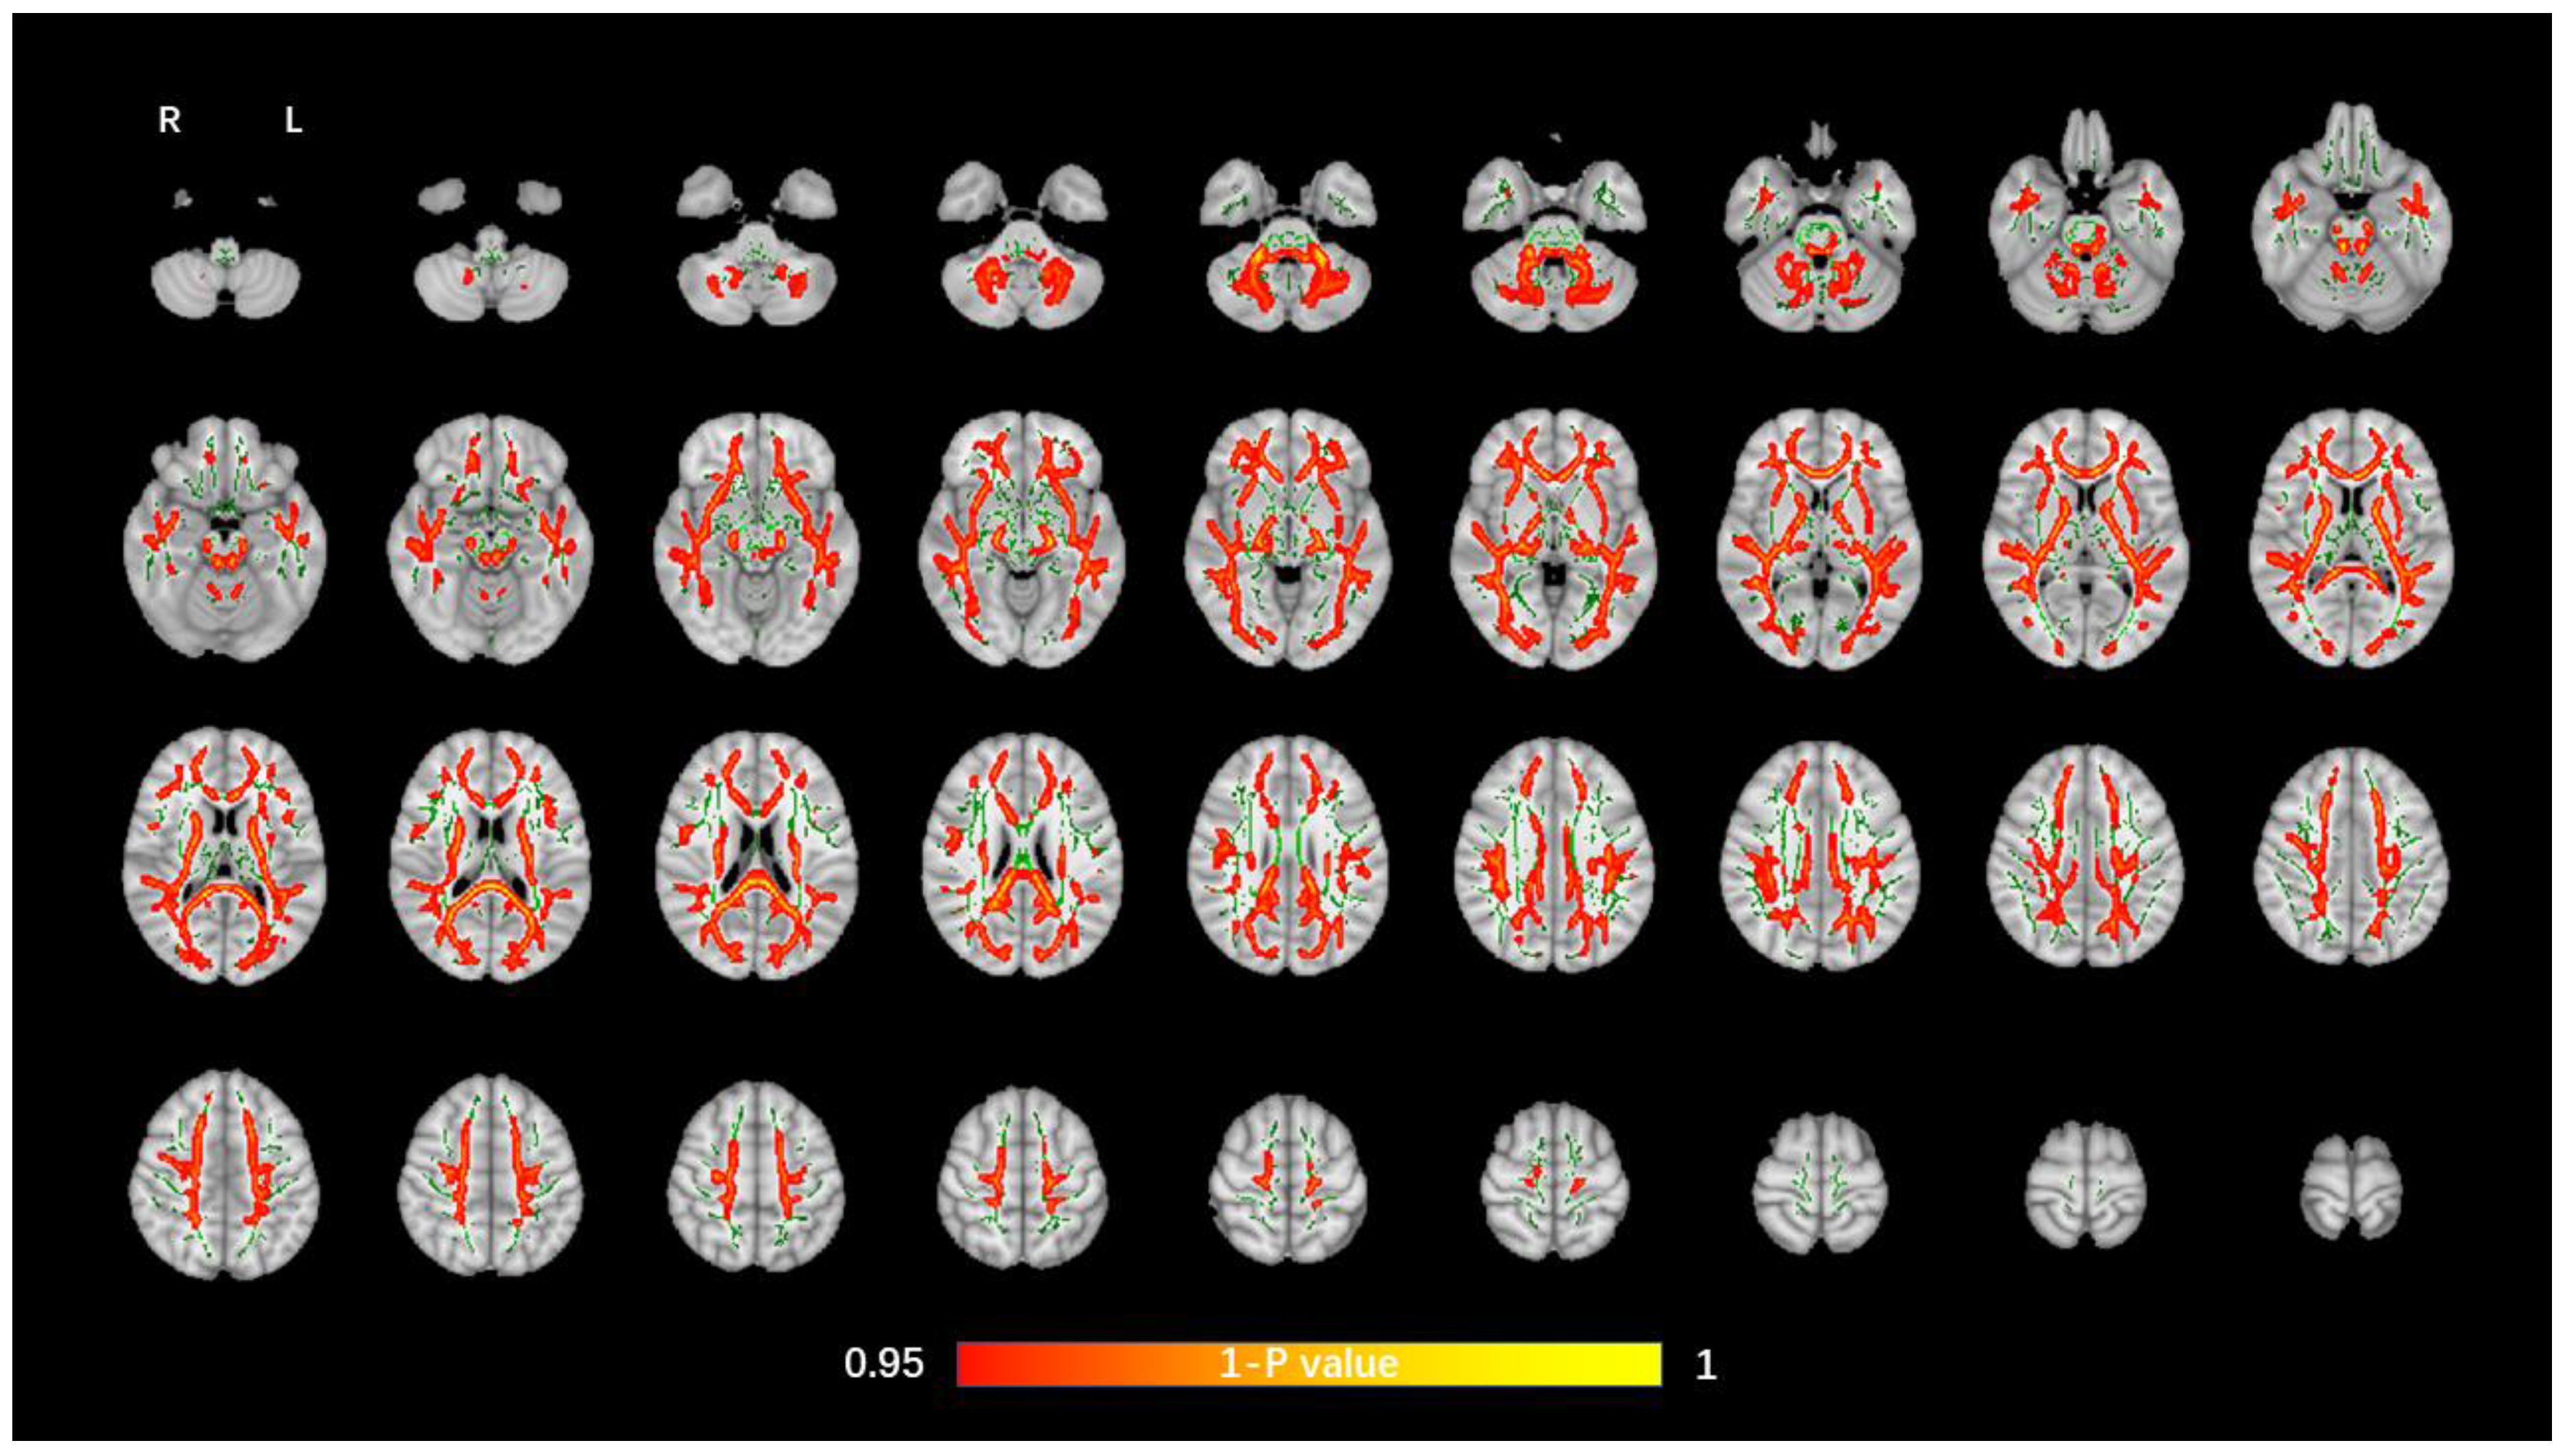

The average FA WM skeleton of all subjects was constructed in TBSS analyses, as shown by the green line in Figure 1, Figure 2, Figure 3 and Figure 4. An analysis of variance of voxel level was carried out on the WM skeleton, and the differences among the three groups were compared. p < 0.05 after FWE correction based on TFCE was statistically significant. Statistically significant areas were expanded to better show the position of WM fiber bundles, as shown in the red part in Figure 1, Figure 2, Figure 3 and Figure 4. The statistical results showed that the DTI indexes of most fiber bundles were statistically significant. There was a significant statistical difference in the FA, MD, AD, and RD values of the FMI, FMA, IFOF, SLF, ILF, ATR and corticospinal tract (CCT) among the three groups (p < 0.05; Figure 1, Figure 2, Figure 3 and Figure 4).

Figure 3.

Voxel-wise TBSS analysis results of AD images among the WML-VCIND, WML-VaD, and HC groups. Green represents the mean WM skeleton of all subjects. Red-yellow (thickened for better visibility) represents regions with a significant F-test statistical difference (p < 0.05, TFCE-based FWE-corrected). TBSS, tract-based spatial statistics; AD, axial diffusivity.